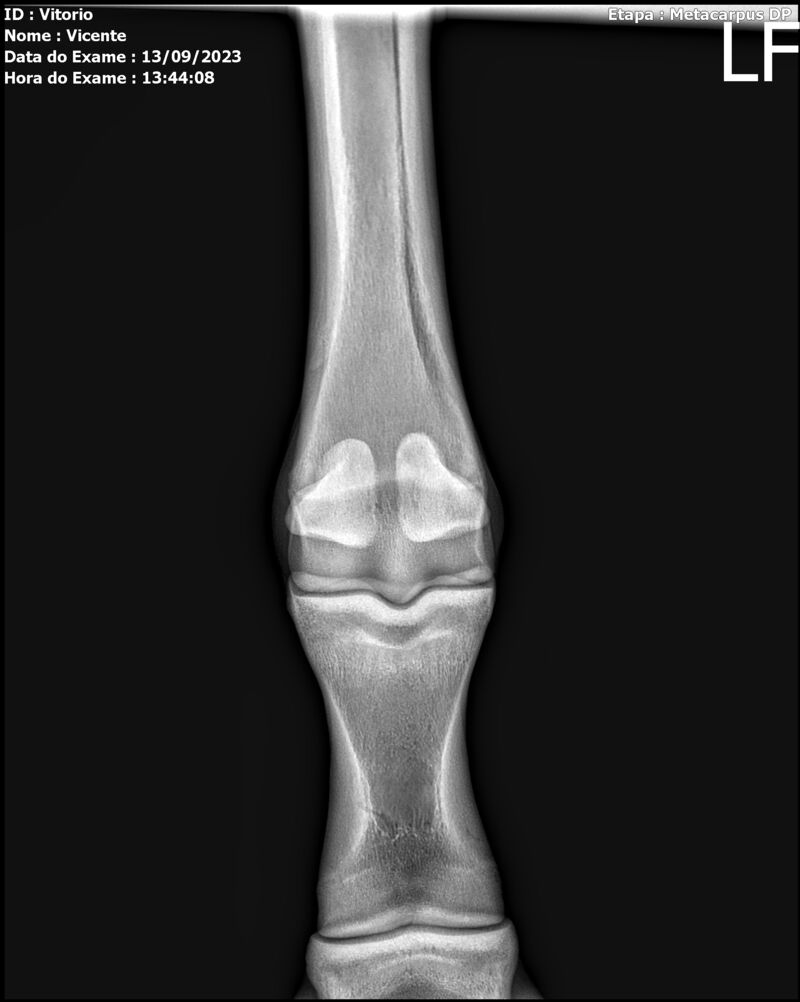

LOTE 13

THUNDER ZC

Raça: BRASILEIRO DE HIPISMO

Sexo: MACHO - POTRO

Nascimento: 17/09/2022

Altura Aproximada: 1,54

Pel.: CASTANHO

Registro: EM AND

Vend.: VICENTE CONTE

Local : PORTO FELIZ/SP